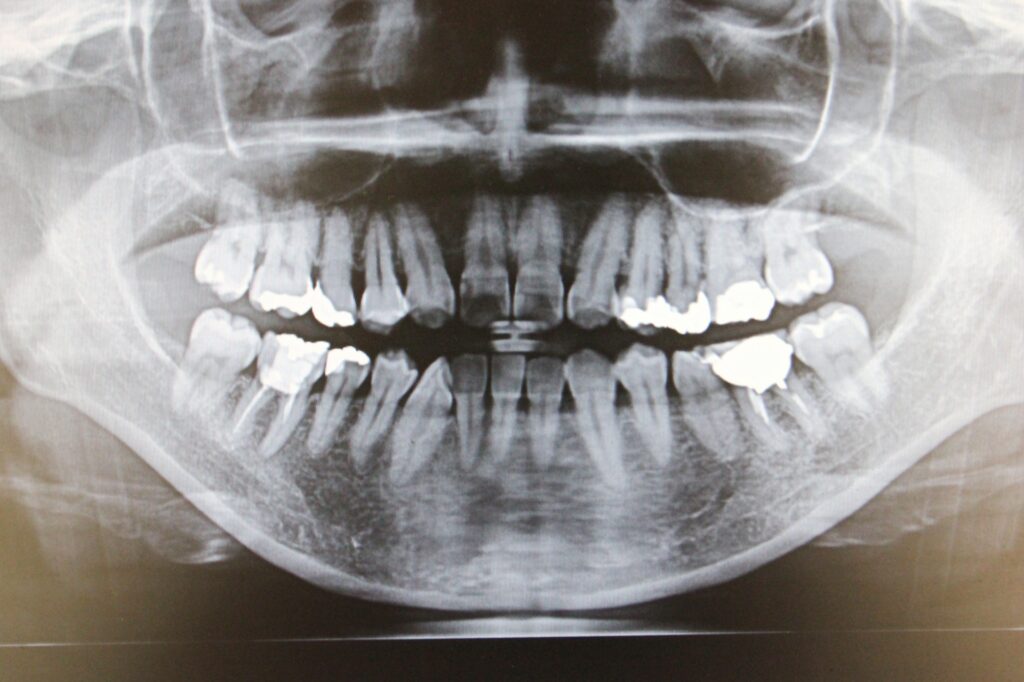

🦷 パノラマレントゲン・

10枚法X線写真(レントゲン)

パノラマレントゲン

デンタルX線写真10枚法

歯周病の治療計画を立てる上で、レントゲン撮影は目に見えない「歯を支える骨」の状態を知るために欠かせない検査です。

当院では、主に「パノラマレントゲン」と「デンタルX線写真(10枚法など)」の2種類を撮影します。

1. パノラマレントゲン(お口全体を映す写真)

パノラマレントゲンは、お口全体の状態を一枚の大きな写真として撮影するものです。

これにより、歯周病の進行状況だけでなく、顎の関節や親知らず、お口全体の骨の量とバランスを俯瞰的に把握できます。

例えるなら、「お口全体の地図」のような役割を果たし、これから行う治療の全体像と優先順位を決定するために必要不可欠です。

このように、広範囲を把握する「パノラマ」と、詳細を分析する「デンタル」を組み合わせることで、歯周病の状態を診断し、最適な治療計画をご提案しています。